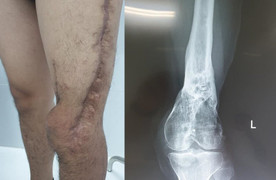

Không chỉ người già, số lượng người trẻ cần phục hồi chức năng cũng không hề ít. Các bệnh nhân sau phẫu thuật hay không phẫu thuật như tai biến mạch máu não; các bệnh lý về khớp; chấn thương thể thao; chấn thương lao động; chấn thương trong sinh hoạt hàng ngày… cũng đều cần phục hồi chức năng.

Khác với Nhật Bản, ở Việt Nam, ngoài tỷ lệ người già cần chăm sóc thì số bệnh nhân cần phục hồi chức năng sau tai nạn rất nhiều, đặc biệt là tai nạn giao thông. Tuy nhiên, hiện tỷ lệ bác sĩ và kỹ thuật viên chăm sóc lượng bệnh nhân đó thì thiếu, không đủ lực lượng chăm sóc từ A-Z như ở Nhật, không chăm sóc chuyên sâu. Người bệnh chủ yếu dựa vào sự chăm sóc của gia đình chứ chưa có một mô hình chăm sóc sức khỏe và phục hồi chức năng toàn diện, linh hoạt.